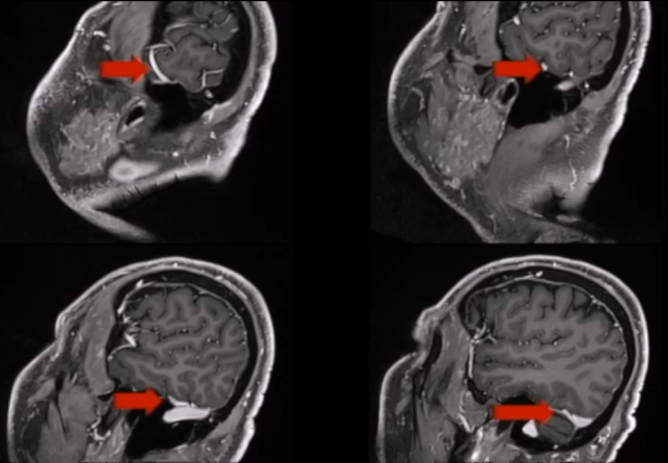

第一步是术前精准评估:通过MRI确认脑干无水肿,CT扫描逐一评估肿瘤钙化程度、岩尖气化范围、颈静脉球与内耳道的位置关系,每一个解剖细节,都是术中安全操作的前提。

第二步是术前血管栓塞:在正式手术前,经介入手段在咽升动脉处置入栓塞线圈,提前切断肿瘤供血来源,大幅压缩术中出血量,为后续操作争取更充裕的术野空间。

术后MRI显示:肿瘤几乎完全切除,脑干压迫已彻底解除。术后CT未见任何并发症,颅骨修复状态良好。